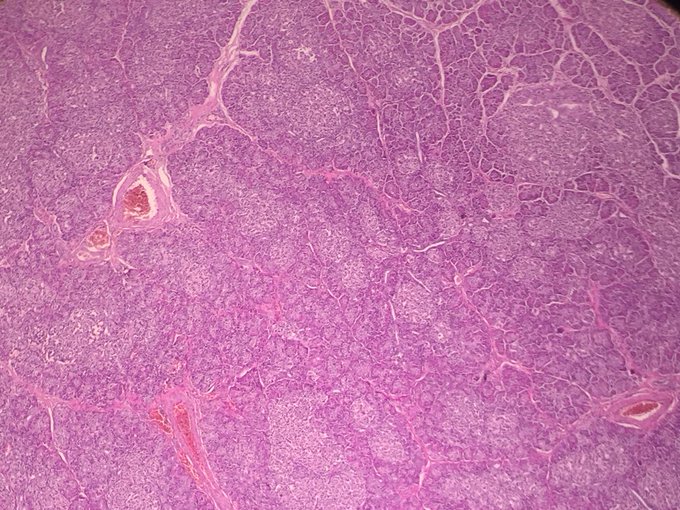

#Pancreas, l'économiser en réduisant les sucres et en bougeant ! - https://t.co/Hc14OdpL0A - #Diabète #Diabétique #ForzaPersona #Sucre https://t.co/zxWYGOYYhZ